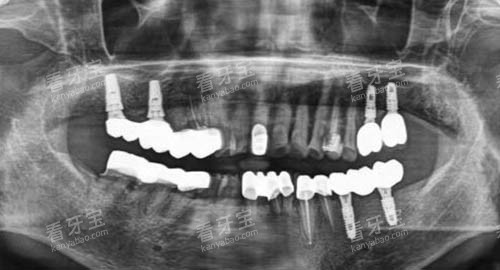

此外,德瓦口腔还引进了一系列国内外较高的口腔诊疗设备。

如口腔 CT 机,它能够清晰地显示牙齿和颌骨的内部结构,为医生的诊断和治疗提供较准的依据。